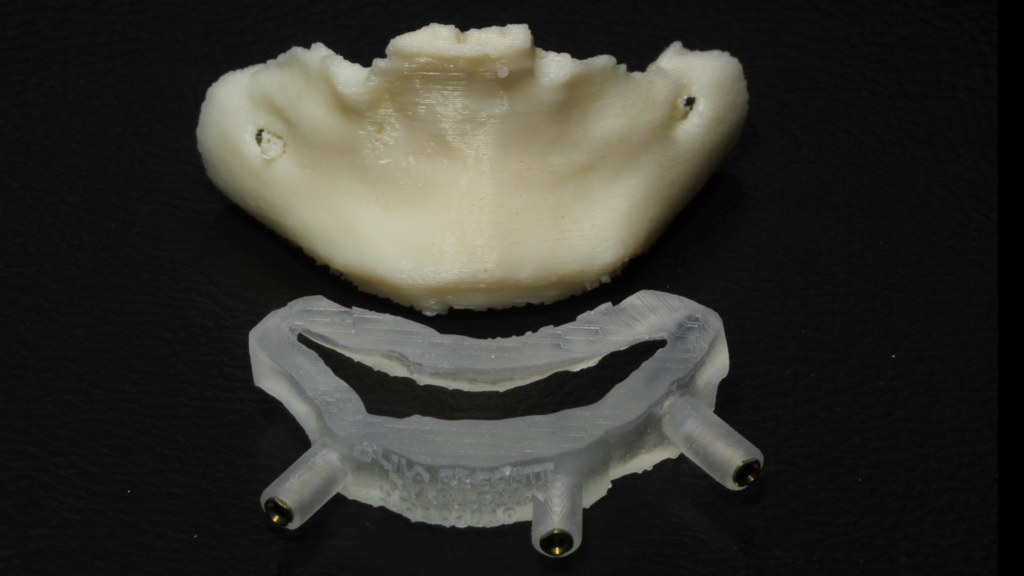

A seguir, vamos ilustrar um caso de cirurgia com 2 guias ósseos, 1 de recorte ósseo e outro de perfuração:

Através do programa Blue Sky (em parceria com a empresa Odontoplanning), foi feito planejamento guiado com 2 guias. O primeiro guia de recorte ósseo, tem como objetivo o recorte e aplainamento ósseo, deixando uma altura óssea mais uniforme entre a região posterior e anterior da mandíbula.

Através da imagem do osso recortado é planejada a guia de perfuração que vai se encaixar de uma maneira perfeita no osso recortado.

Lembrando que essas guias serão apoiadas exclusivamente no osso, sem envolvimento de mucosa, portanto há que se fazer incisão e descolamento mucoperiostal suficiente para o encaixe da guia.